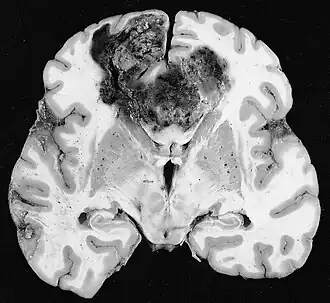

Glioblastoom

De meest voorkomende en kwaadaardige gliaceltumoren zijn glioblastomen. Ze bestaan voornamelijk bij volwassenen uit een heterogene massa van slecht gedifferentieerde astrocytoomcellen. Ze komen meestal voor in de hersenhelften, meer zelden in de hersenstam of het ruggenmerg. Behalve in zeer zeldzame gevallen, zoals alle hersentumoren, reiken ze niet verder dan de structuren van het centrale zenuwstelsel.

Glioblastoom kan ontstaan uit een diffuus (II. graad) of een anaplastisch astrocytoom (III. graad) ontwikkelen. In het laatste geval wordt het secundair genoemd. Wanneer het echter optreedt zonder antecedenten of bewijs van eerdere maligniteit, wordt het primair genoemd. Glioblastomen worden behandeld met chirurgie, bestraling en chemotherapie. Ze zijn moeilijk te genezen en er zijn maar weinig gevallen die langer dan drie jaar overleven.

Aan -MRI toont een intracraniële tumor als een massieve laesie die na gebruik van het contrastmiddel meer luminescent kan worden. Er is echter altijd een signaalafwijking in -Magnetic resonance imaging, die de aanwezigheid van neoplasie of vasogeen oedeem aangeeft. Gewoonlijk is verhoogde luminescentie (contrastversterking) indicatief voor een tumor met een hogere graad van maligniteit. Kenmerkend voor glioblastoom is een contrastring, waarbij het lichtgevende deel overeenkomt met het vitale deel van de kwaadaardige tumor en het donkerdere -hypointens gebied dat overeenkomt met weefselnecrose.